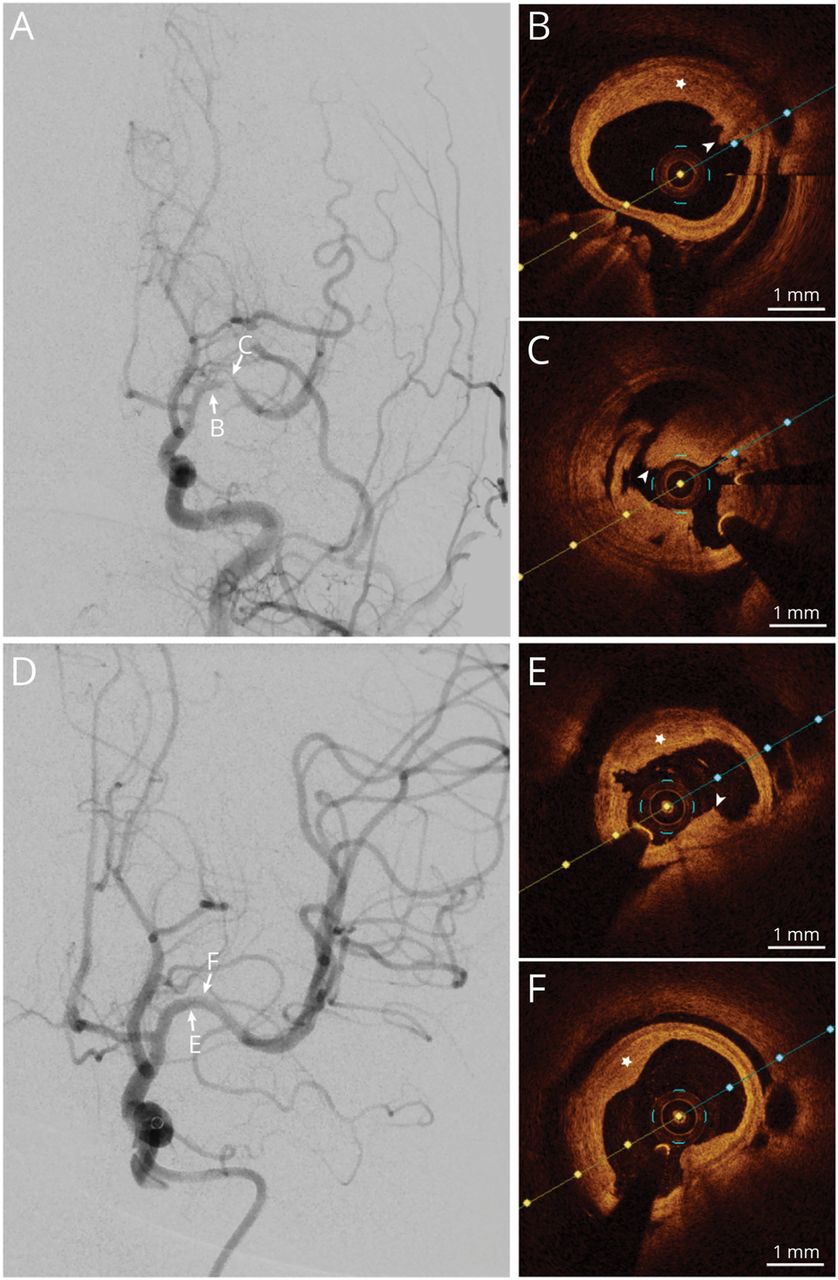

一个24岁的人急性大脑中动脉闭塞离开接受了血栓切除术。罪魁祸首病变的观察充盈缺损后第一个凝块检索(图,一个)。术中光学相干断层扫描(OCT)进行探讨病因,这暴露了一个完整的纤维斑块纤维帽和管腔内的白色血栓(图中,B和C)。与第二个完全实现再灌注凝块检索(图D)。重复10月证实血管再通和斑块破裂的缺失(图中,E和F),这表明大型动脉动脉粥样硬化斑块侵蚀造成了原位血栓形成。1辅助抗血小板治疗管理,功能独立达到90天。10月为洞察内在血管壁疾病提供了高空间分辨率。2它可以作为一个健壮的工具在血栓切除术模棱两可的病原学诊断,揭示个性化辅助治疗和适当的二级预防策略,改善的结果。

(一)第一个凝块检索后充盈缺损。(B和C) 10月显示纤维斑块与完整的纤维帽(low-attenuating signal-rich病变,明星)和白色血栓(经管low-attenuating, signal-rich质量,箭头)。(D)成功的第二个凝块检索。10月(E和F)重复确认未破裂斑块和残余白色血栓。10月=光学相干断层扫描。